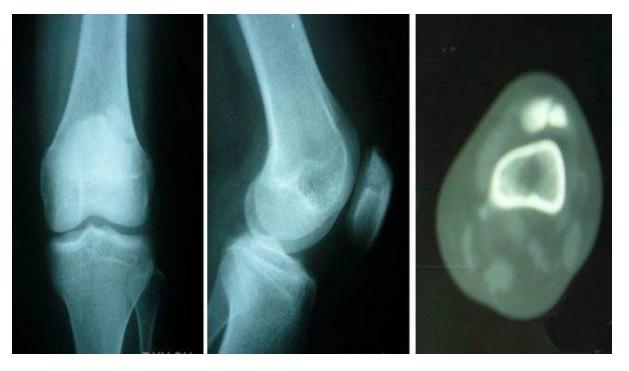

7、剥脱性骨软骨炎

关节内的骨软骨病,病因不明,关节软骨和软骨下骨变性和再钙化,最常见于股骨内髁,模糊的、定位不清的膝关节疼痛,有晨僵,反复的关节内积液(轻度)。如有游离体,可发生交锁症状。股四头肌萎缩,受累股骨髁关节软骨面压痛。

X线平片显示骨软骨病损或关节内游离体。如怀疑剥脱性骨软骨炎,摄片应包括前后位、后前隧道位、侧位和髌股关节切线位。